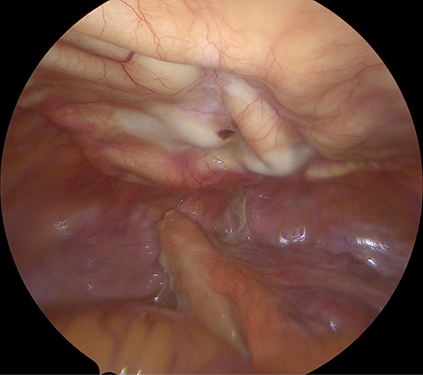

The patient was brought to the operating room where she underwent laparoscopic appendectomy. During the laparoscopy it was observed that the Strattice acellular dermal matrix was covered with peritoneum and there were no adhesions of the bowel to the abdominal wall.

The appendix was removed in a straightforward manner without additional adhesiolysis of adjacent bowel and no removal of bowel attached to the acellular dermal matrix (Figure 4) (Figure 5).

Figure 4 Laparoscopic view at the time of appendicitis showing Strattice acelluar dermal matrix overed with vascularied peritoneam located at the top of the image. The inflammed appendix is present at the bottom of the screen. There were no adhesions between the bowel and the anterior abdominal wall and Strattice acellular dermal matrix.